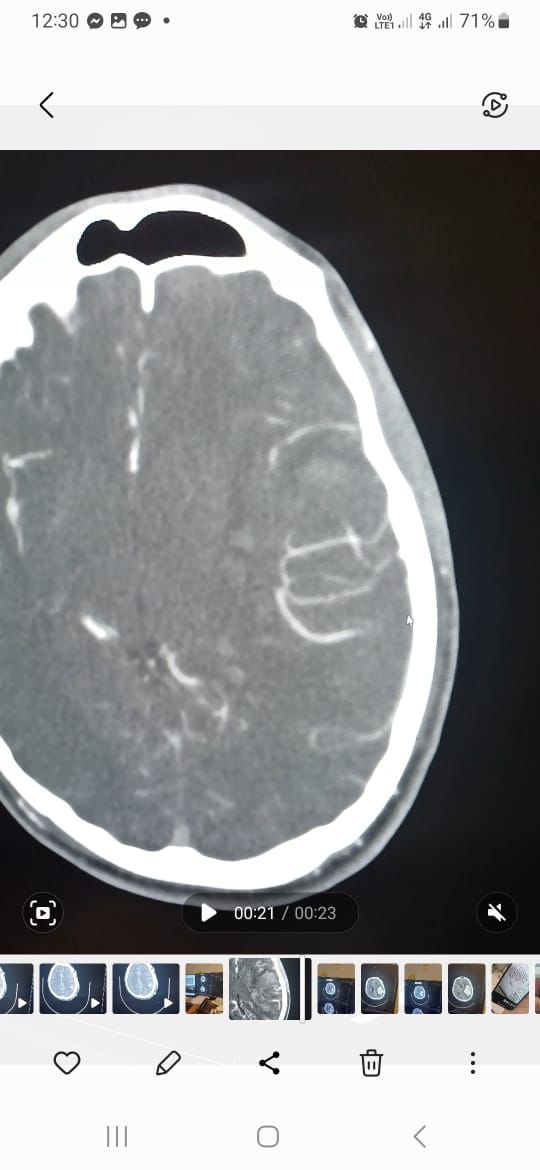

تمكن بفضل من الله فريق طبي من  قسم جراحة المخ والاعصاب  بمستشفى الملك خالد التابع للتجمع الصحي بتبوك من انقاذ حياة شاب بالعشرين من عمره وصل الى قسم الطوارئ وهو في حالة فقدان للوعي وبعد عمل الفحوصات اللازمة وتصوير الاوعية الدموية الدماغية تبين وجود نزيف دماغي حاد في الجهة اليسرى كذلك وجود تشوه خلقي دموي وعائي كبيرا جدا.

وأوضح الفريق الطبي من  قسم جراحة المخ والاعصاب  بالتجمع بانه تم فورا ادخال المريض الى غرفة العمليات واجراء استئصال للأوعية الدموية مجهريا حيث استغرق اجراء العملية أكثر من 5 ساعات تكللت ولله الحمد بالنجاح كما تم تحويل المريض لقسم التنويم بمتابعة وإشراف الفريق الطبي.